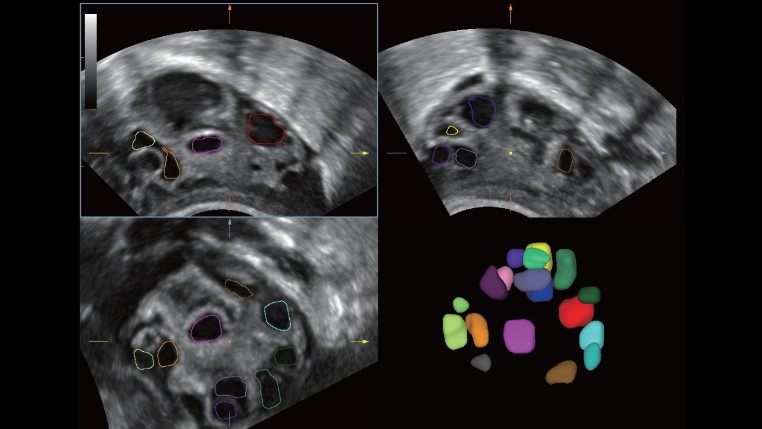

Dual-Volume

–ü–Ψ–¥–¥–Β―Ä–Ε–Κ–Α –Κ–Ψ–Ϋ–≤–Β–Κ―¹–Ϋ–Ψ–≥–Ψ –Η –≤–Ϋ―É―²―Ä–Η–Ω–Ψ–Μ–Ψ―¹―²–Ϋ–Ψ–≥–Ψ –Ψ–±―ä–Β–Φ–Ϋ―΄―Ö –¥–Α―²―΅–Η–Κ–Ψ–≤, a ―²–Α–Κ–Ε–Β ―¹–Ψ–Ψ―²–≤–Β―²―¹―²–≤―É―é―â–Η―Ö –Ω―Ä–Ψ–≥―Ä–Α–Φ–Φ–Ϋ―΄―Ö 3D/4D –Ψ–Ω―Ü–Η–Ι, DC-40 ―¹ Full HD –Ω―Ä–Β–¥―¹―²–Α–≤–Μ―è–Β―² ―Ä–Β―à–Β–Ϋ–Η–Β ?Dual-Volume?, –Κ–Ψ―²–Ψ―Ä–Ψ–Β –Ψ–±–Β―¹–Ω–Β―΅–Η–≤–Α–Β―² –Ω–Ψ–Μ–Ϋ―΄–Ι ―¹–Ω–Β–Κ―²―Ä –Ϋ–Β–Ψ–±―Ö–Ψ–¥–Η–Φ–Ψ–Ι –¥–Η–Α–≥–Ϋ–Ψ―¹―²–Η–Κ–Η –¥–Μ―è –Ω–Μ–Α–Ϋ–Η―Ä–Ψ–≤–Α–Ϋ–Η―è ―¹–Β–Φ―¨–Η, –Ψ―² –Ω―Ä–Β–Ϋ–Α―²–Α–Μ―¨–Ϋ―΄―Ö –Ψ–±―¹–Μ–Β–¥–Ψ–≤–Α–Ϋ–Η–Ι, –≤–Κ–Μ―é―΅–Α―è –Ω–Μ–Α–Ϋ–Η―Ä–Ψ–≤–Α–Ϋ–Η–Β –Η –Ω―Ä–Ψ–≤–Β–¥–Β–Ϋ–Η–Β –Ω―Ä–Ψ―Ü–Β–¥―É―Ä―΄ –≠–ö–û, –¥–Ψ –≤–Β–¥–Β–Ϋ–Η―è –±–Β―Ä–Β–Φ–Β–Ϋ–Ϋ–Ψ―¹―²–Η.